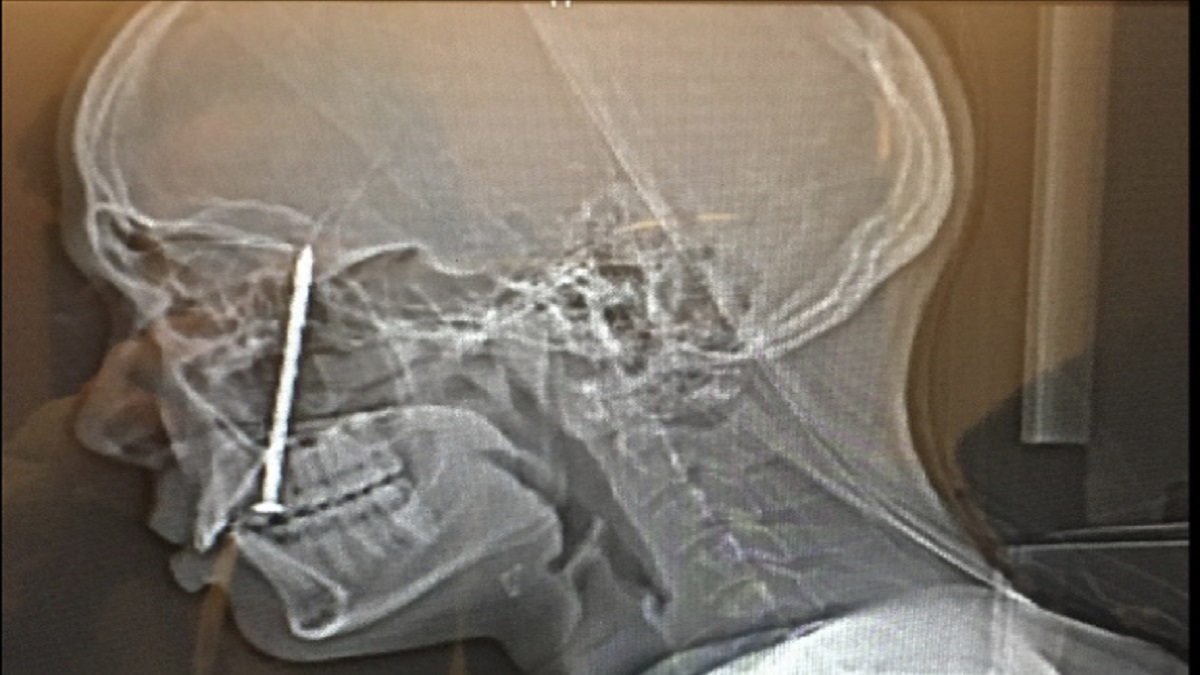

وكان كاهاي (28 عاماً) وهو نجار متدرب يثبت أرضيات من الخشب الرقائقي بمسدس المسامير عندما انطلق مسماران في وقت واحد من مسدسه، واخترق أحدهما وجهه بتلك الطريقة المأساوية، ففتح جانباً من ذقنه وشفته واستقر في لسانه ورأسه.

وفي حالة صدمة، وضع كاهاي الأداة أرضاً ونزل وهو ينزف إلى الطابق السفلي للإبلاغ عن الحادث، وعلى الفور نقله زملاؤه إلى عيادة ستانفورد الصحية القريبة للطوارئ، وخضع لعمليات جراحية متعددة لإصلاح لسانه وحنكه وحاجزه الأنفي والجيوب الأنفية، ولإصلاح جمجمته وفكه المكسور.

كما جاء في الدعوى القضائية المرفوعة في المحكمة الجزئية الأميركية في سان فرانسيسكو أن أخصائيي جراحة الأعصاب والأذن والأنف والحنجرة قاموا بتقييم حالة كاهاي، وقرروا أنه سيحتاج إلى جراحة، لكنه اضطر إلى الانتظار حتى اليوم التالي لإخراج المسمار.